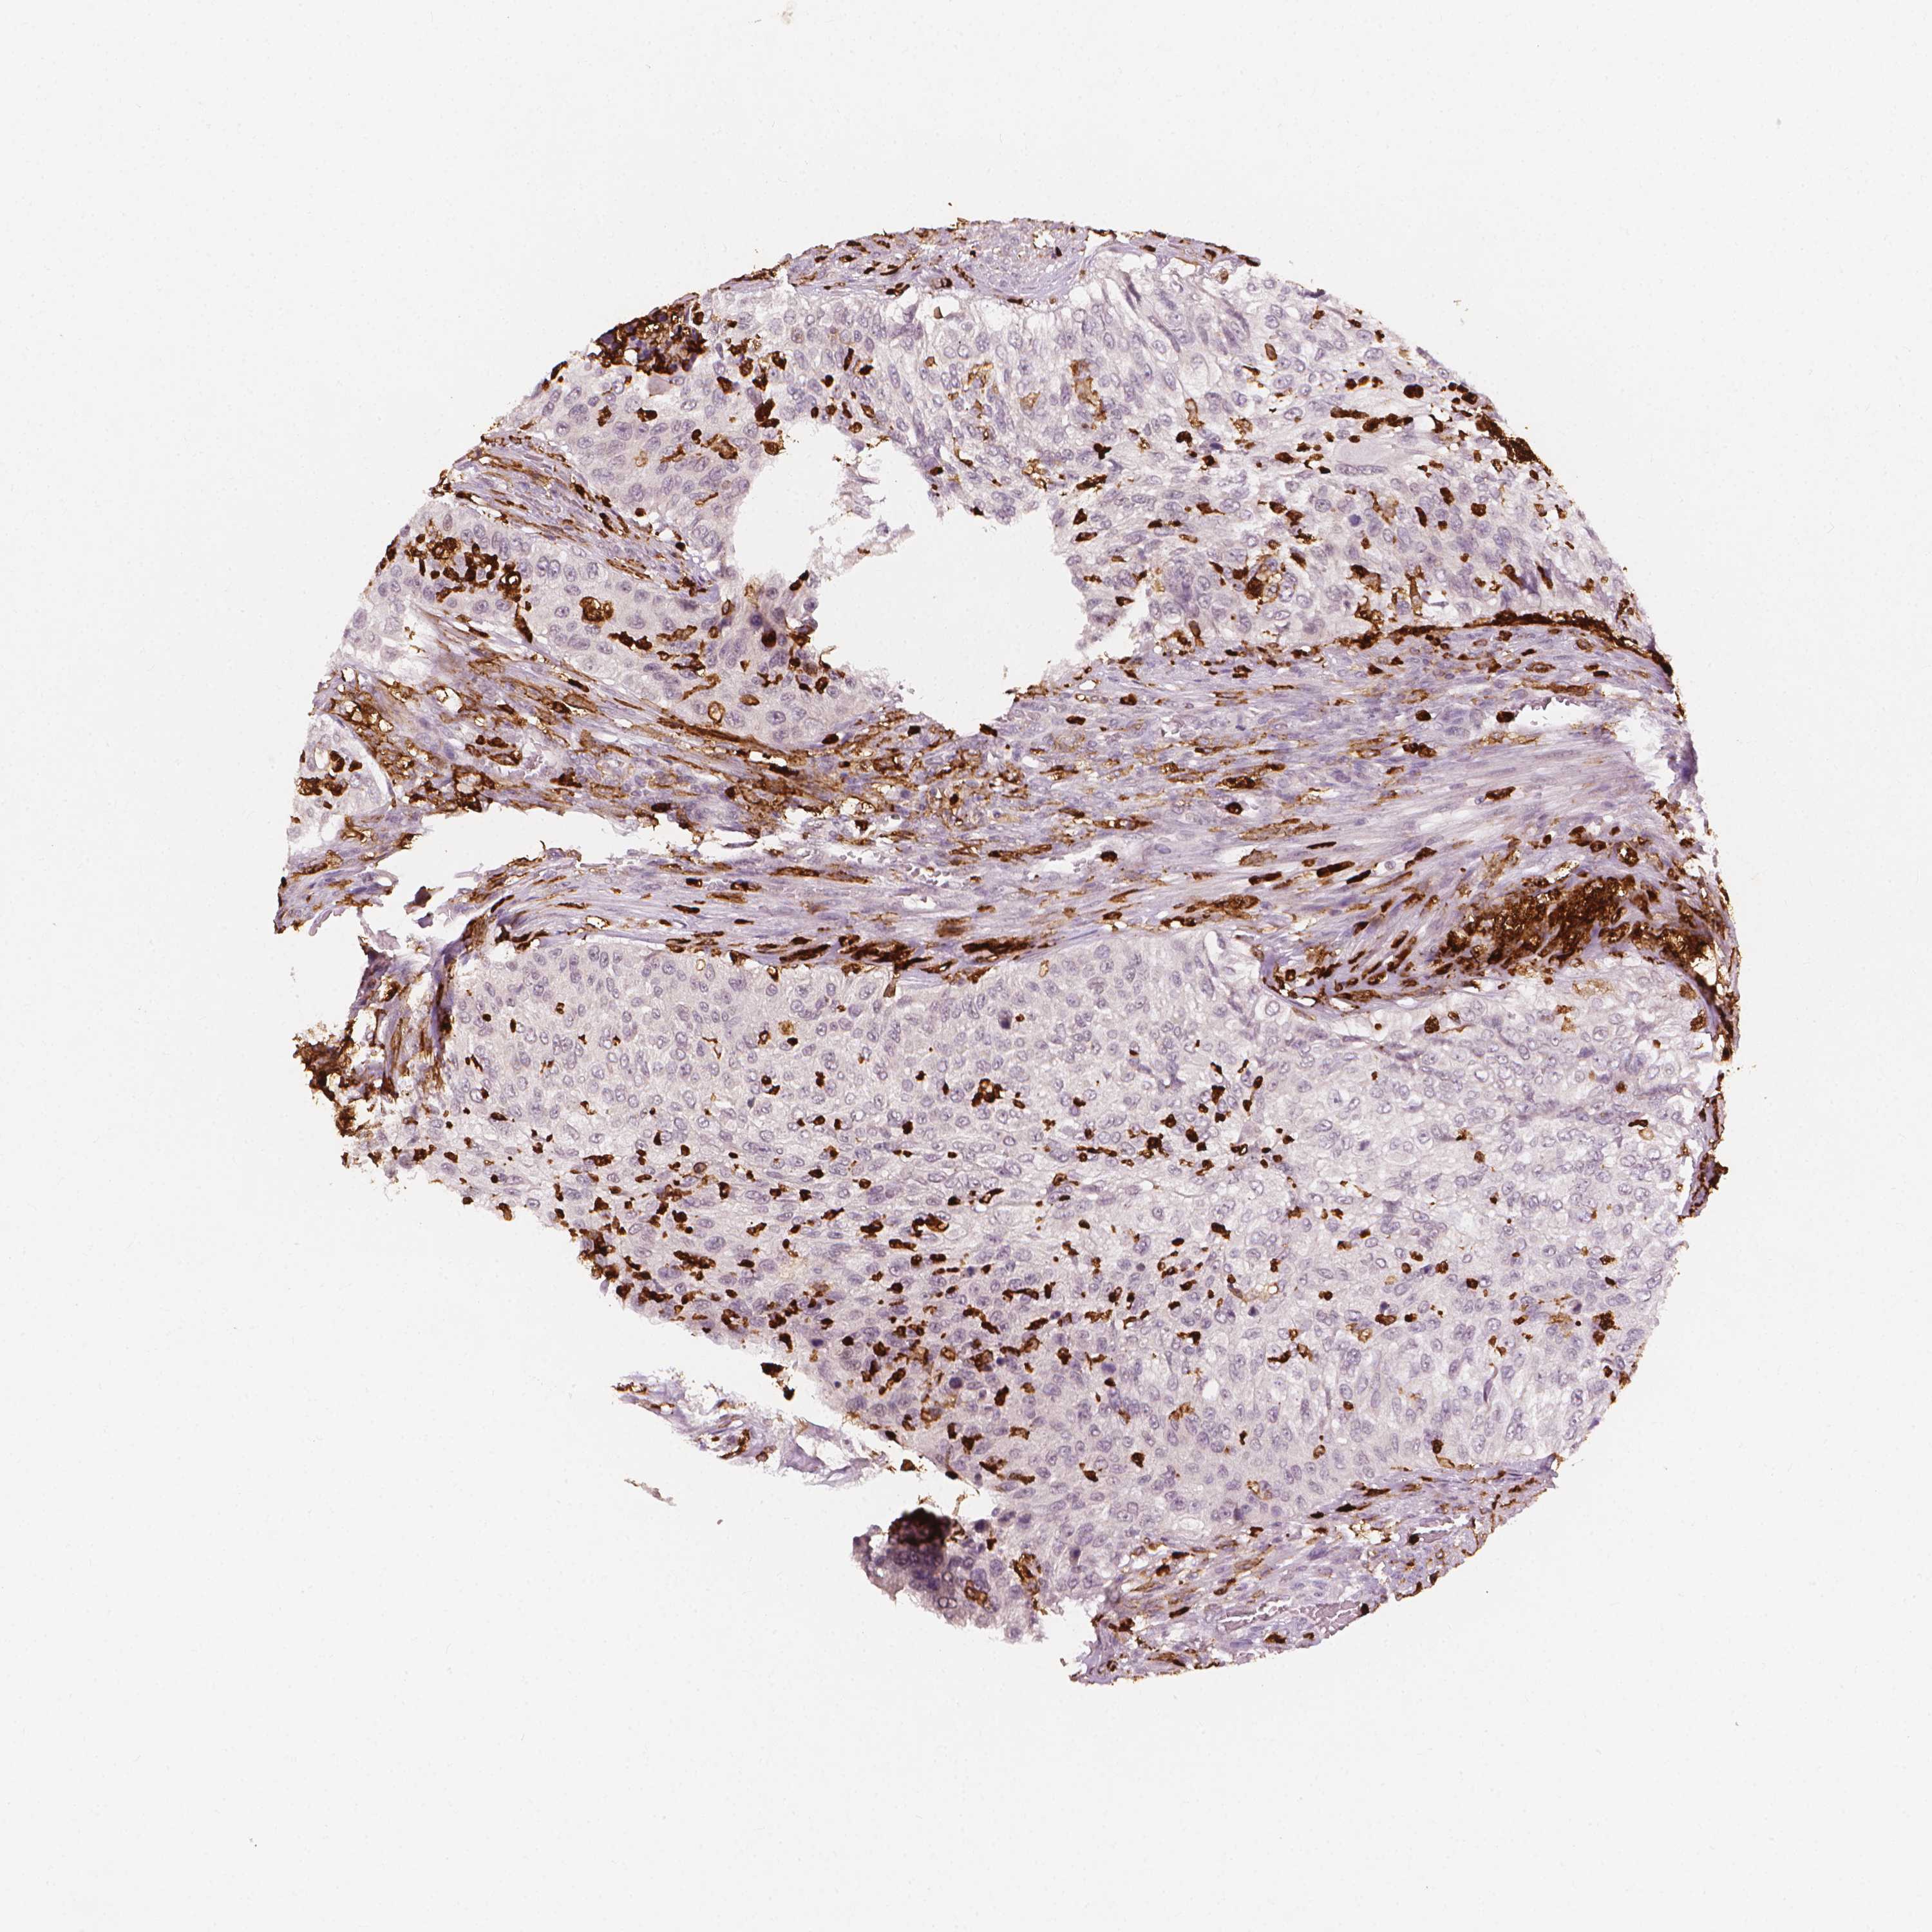

UROTHELIAL CANCER - Protein expressioni

A mouse-over function shows sample information and annotation data. Click on an image to view it in a full screen mode. Samples can be filtered based on level of antibody staining by selecting one or several of the following categories: high, medium, low and not detected. The assay and annotation is described here.

Antibody stainingi

Antibody staining in the annotated cell types in the current human tissue is reported as not detected, low, medium, or high, based on conventional immunohistochemistry profiling in selected tissues. This score is based on the combination of the staining intensity and fraction of stained cells.

Each image is clickable and will lead to virtual microscopy that enables deeper exploration of all samples and also displays staining intensity scores, fraction scores and subcellular localization as well as patient and tissue information for each sample.

Antibody HPA072667

Antibody CAB009492

Staining

High

Medium

Low

Not detected

Intensity

Strong

Moderate

Weak

Negative

Quantity

>75%

75%-25%

<25%

None

Location

Nuclear

Cytoplasmic/membranous

Cytoplasmic/membranous,nuclear

Urothelial carcinoma, High grade

Urothelial carcinoma, Low grade

Urothelial carcinoma, NOS